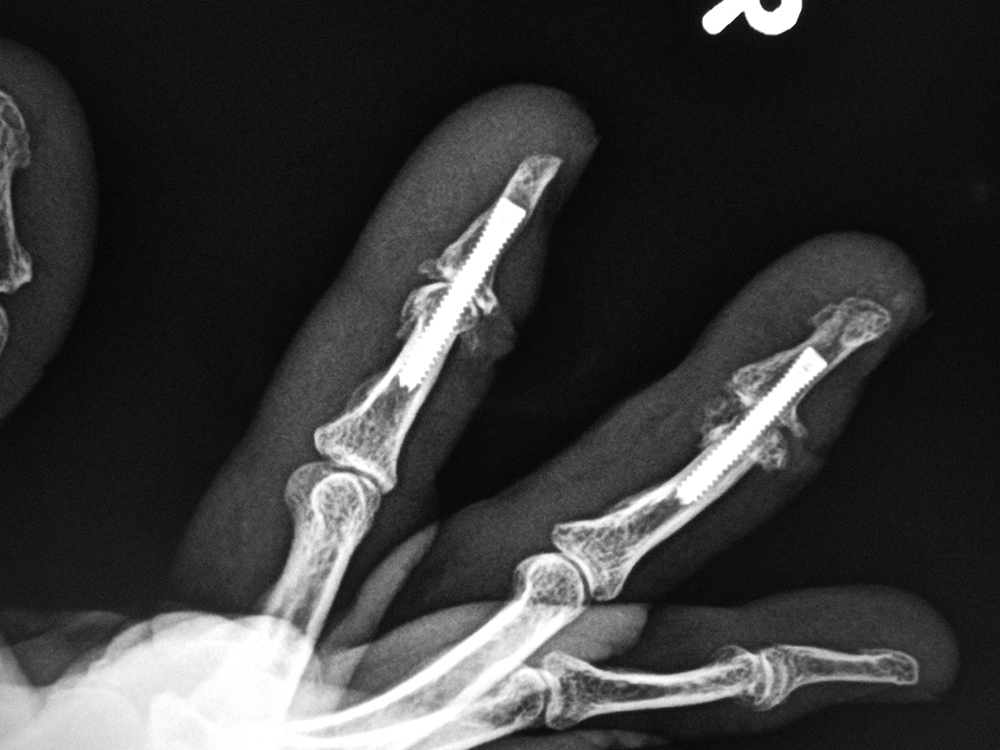

A similar screw is the Acutrak screw. It is headless with variable thread pitch on either end, but it does not have an unthreaded central shank (figure: Acutrak screw) (figure: Acutrak screws and endobuttons). It is very commonly used for the treatment of finger and wrist fractures. The Smart (toe) implant is a product of Stryker specifically designed for interdigital fusion of fingers or toes and other small bones. It is sometimes used in conjunction with K-wires and small fixation screws (figure: Smart toe implants).

| Accutrak screws

| The Accutrak screws are used for arthrodesis of the distal interphalangeal joints of the right index and long fingers in a woman with severe osteoarthritis.